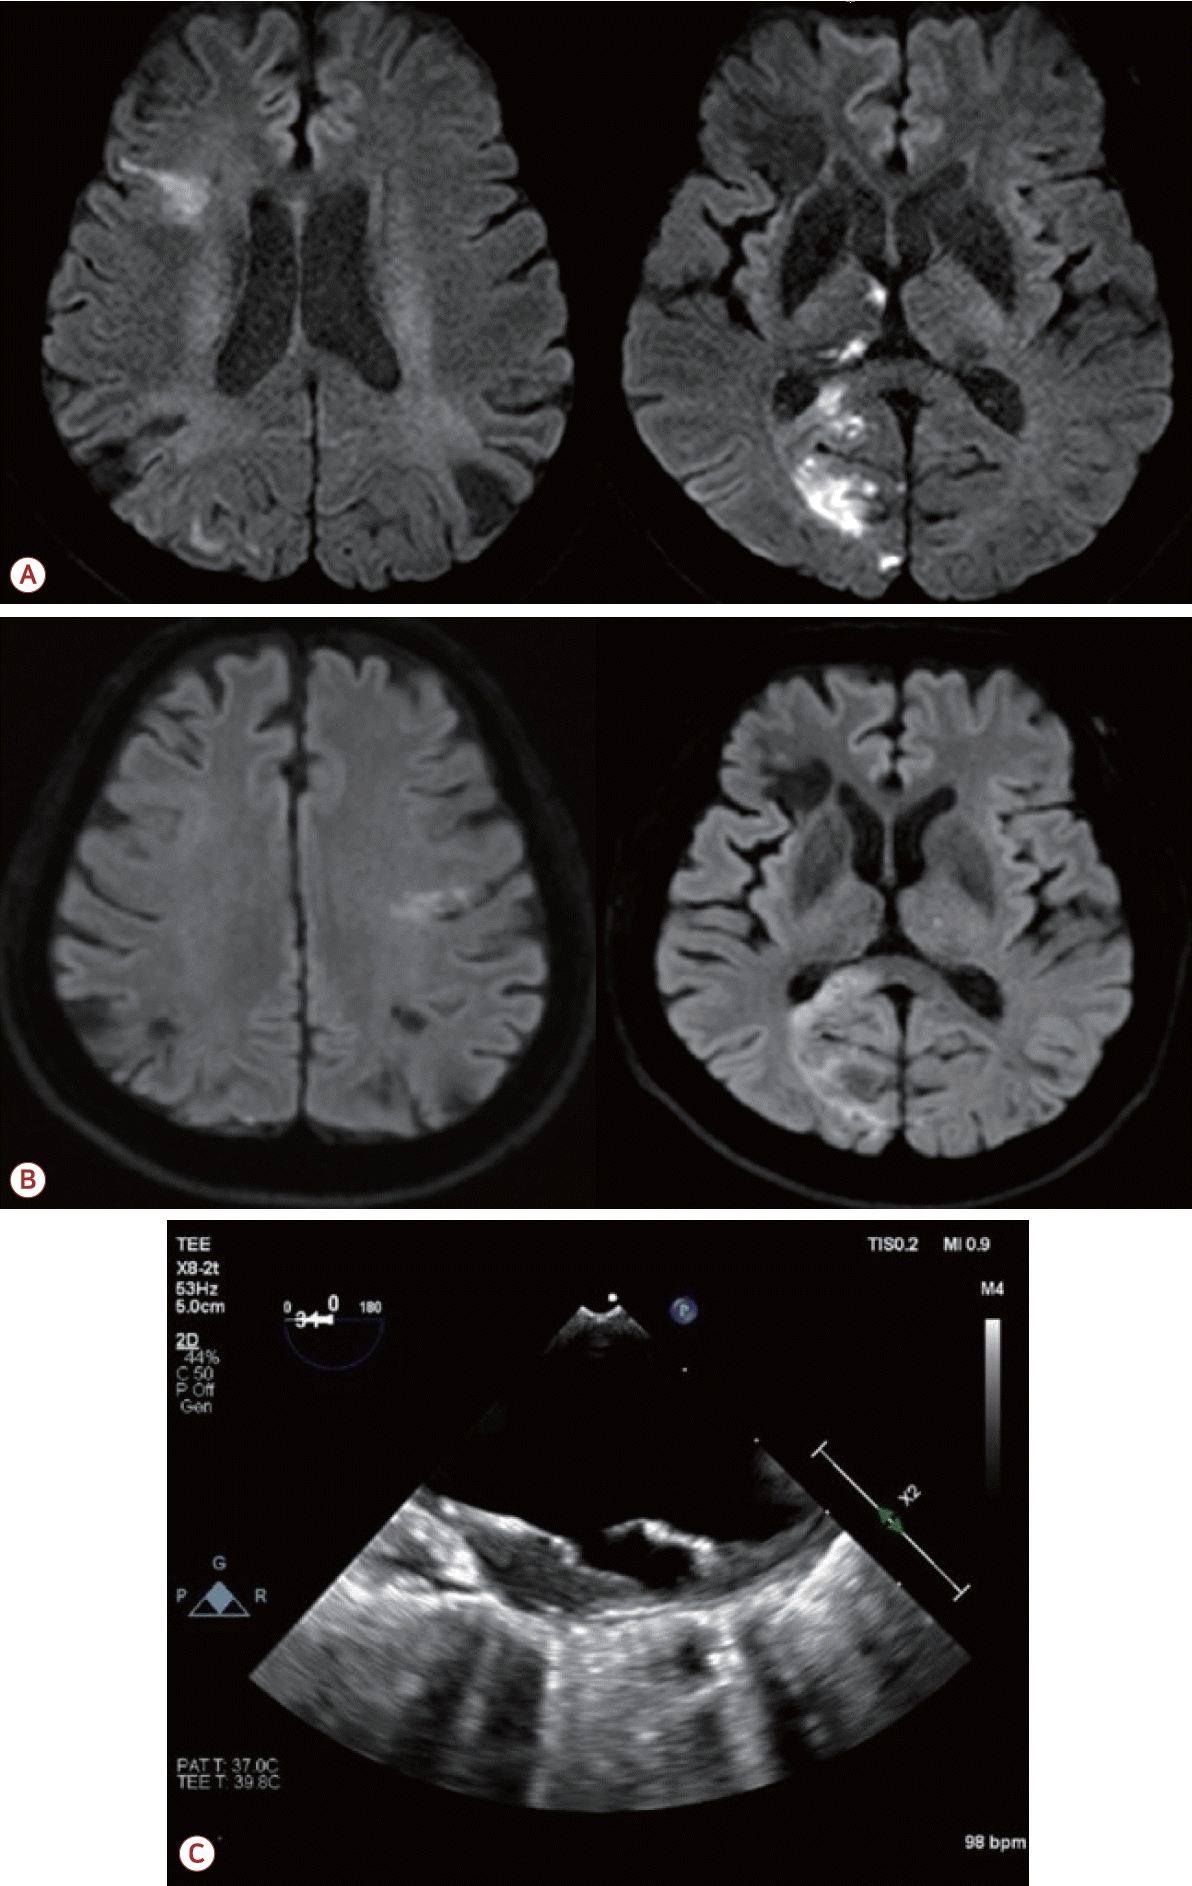

73세 남자가 최근 3개월간 반복적인 허혈뇌졸중으로 내원하였다. 환자는 고혈압, 당뇨, 안정협심증의 기저 질환을 가지고 있었다. 초기 뇌자기공명영상(magnetic resonance [MR] imaging)에서 좌측 대뇌반구와 우측 소뇌에 다발성 허혈 병변이 관찰되었으며(Fig. 1-A) 혈관 검사에서는 좌측 내경동맥근위부(internal carotid artery, ICA)에 76.7%의 협착(NASCET 기준)이 확인되었고 동시에 보바인형 대동맥궁(bovine arch, 공통 기시형 변이)이 관찰되었다(Fig. 1-B). 이에 따라 증상성 중증도 이상의 ICA 협착으로 판단하여 좌측 CEA와 이중 항혈소판 요법이 시행되었다. 그러나 시술 2개월 후에 우측 후 대뇌동맥(posterior cerebral artery, PCA)과 우측 중대뇌동맥(middle cerebral artery, MCA) 영역에 재발성 뇌경색이 발생하였고(Fig. 2-A) 한 달 후에는 좌측 MCA와 PCA 영역에 새로운 뇌경색이 재발하였다(Fig. 2-B). 기존에 진행되었던 두개경유도플러 검사에서 심방중격 결손이나 미세색전 신호를 시사하는 소견은 확인되지 않았고 흉부경유심초음파에서 좌심실 박출률은 정상 범위었으며 3일의 홀터 모니터링에서도 심방세동은 관찰되지 않아 심장성 색전은 배제하였다. 반복되는 색전성 병변의 원인을 찾기 위하여 식도유심초음파(transesophageal echocardiography, TEE)가 진행되었으며 대동맥궁 대만부(greater curvature)에 위치한 7 mm 크기의 궤양성(ulcerated), 유동성(mobile)의 고위험 죽경화판(high-risk aortic arch plaque)이 관찰되었다(Fig. 2-C). 추가적인 머리 혈관조영에서는 기존에 확인되었던 좌측 경동맥의 중증도 협착은 호전 상태를 보였으며 보바인형 대동맥궁 및 팔머리동맥에 동맥류성 확장(aneurysmal dilatation)을 확인할 수 있었다(Fig. 3-A). 이에 신경과, 순환기내과, 영상의학과, 심장혈관흉부외과가 포함된 다학제 협의를 통해 단계적 하이브리드 치료가 결정되었다. 첫 번째 단계로 부분 디브랜칭 수술(좌쇄골하-좌총경동맥우회술[partial debranching surgery, left subclavian-left common carotid artery bypass])이 시행되었다. 수술 한 달 후에 팔머리동맥에 스텐트이식편(endovascular brachiocephalic stent-graft)을 삽입하여 팔머리동맥류의 병적 분절을 제거하였다(Fig. 3-B, C). 스텐트 시술 이후 약 1년 6개월이 지난 현재까지도 환자는 지속적으로 이중항혈소판 요법을 유지하면서 추가적인 허혈 사건 없이 안정적으로 추적 관찰 중이다.

(A) Two-month follow-up brain MRI showing recurrent cerebral infarction of right PCA and right MCA territories. (B) Subsequent brain MRI showing new infarctions in the left MCA and right PCA territories. (C) TEE revealing a 7 mm mobile ulcerative plaque at the greater curvature of the aortic arch. MRI; magnetic resonance imaging, PCA; posterior cerebral artery, MCA; middle cerebral artery, TEE; transesophageal echocardiography.